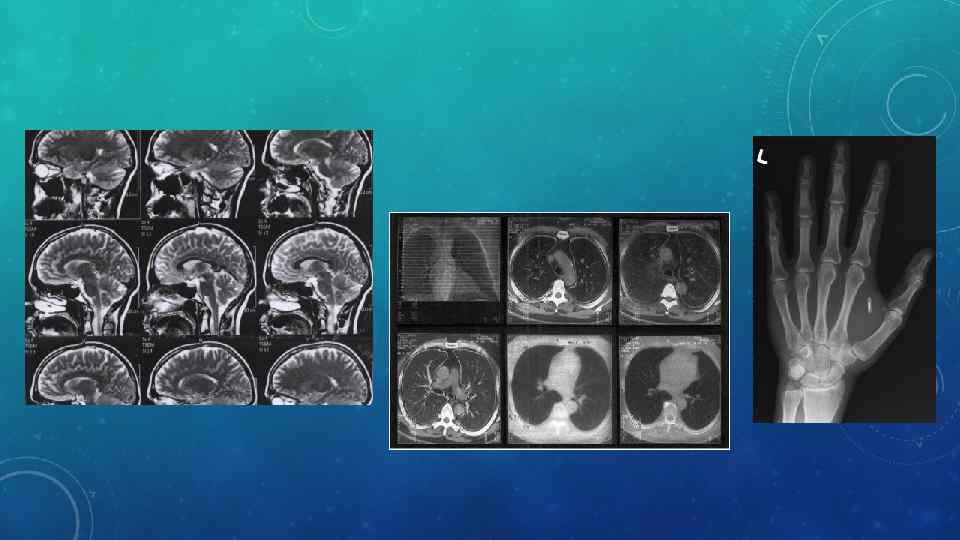

История развития магнитнорезонансной томографии